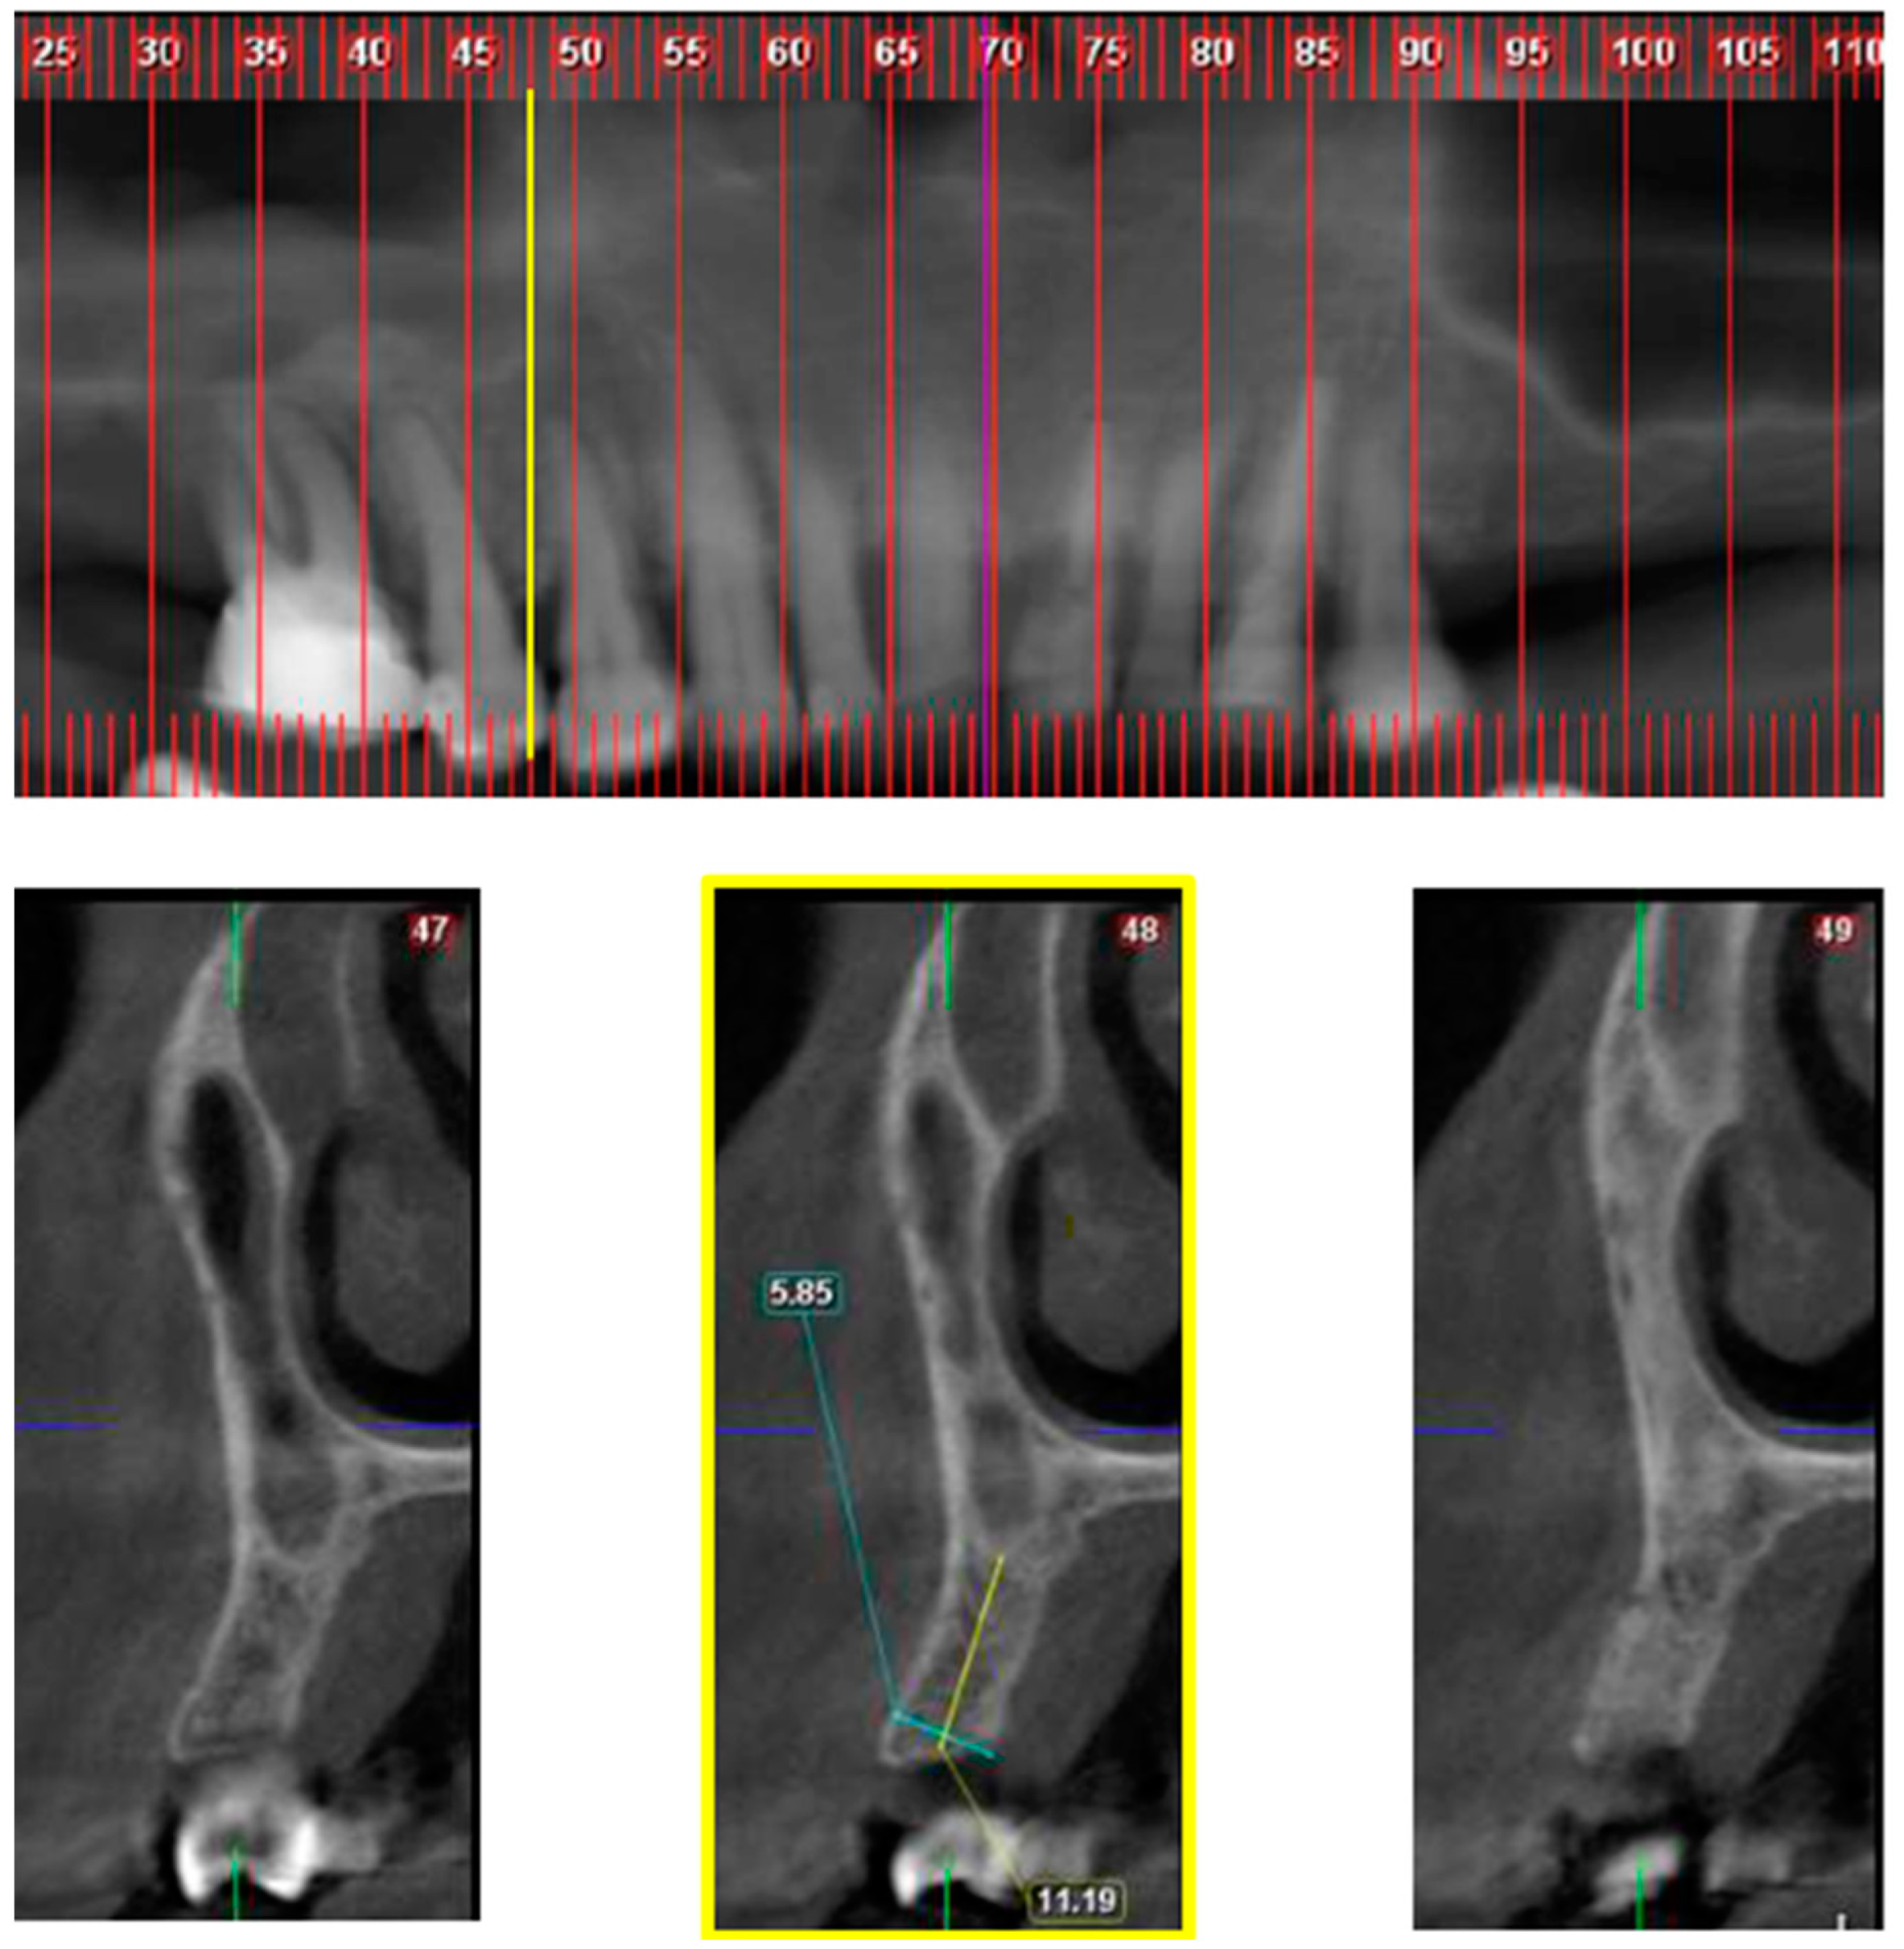

Data were collected from paraxial reconstructions (cross sections) extended from the maxillary canine to the first molar. Two spatial categories were defined, namely classes and divisions.

Classes define the MD location of the nasal/sinus border for each hemi maxilla as demonstrate in Figure 1, Figure 2 and Figure 3. The “border cross section” is the most mesial cross section, in reference to maxillary midline, that above the alveolar crest has both nasal cavity and maxillary sinus cavity. The definition of classes is as follows:

Class 2—“border cross section” is located MD up to the distal edge of 2nd premolar.

Classes 1 and 2 were defined as normal anatomy and Class 3 as “big-nose variant”.

Figure 2. Class 2; Upper part—CBCT panoramic reconstruction; Lower part—from right to left—CBCT cross sections: cross section number 49—demonstrate nasal cavity alone above the alveolar ridge; cross section number 48—yellow line and frame—demonstrate nasal and maxillary sinus “border cross section”, which is located between 1st and 2nd premolars, defined as Class 2; cross section number 47—demonstrate one cross section distal to the “border cross section”.